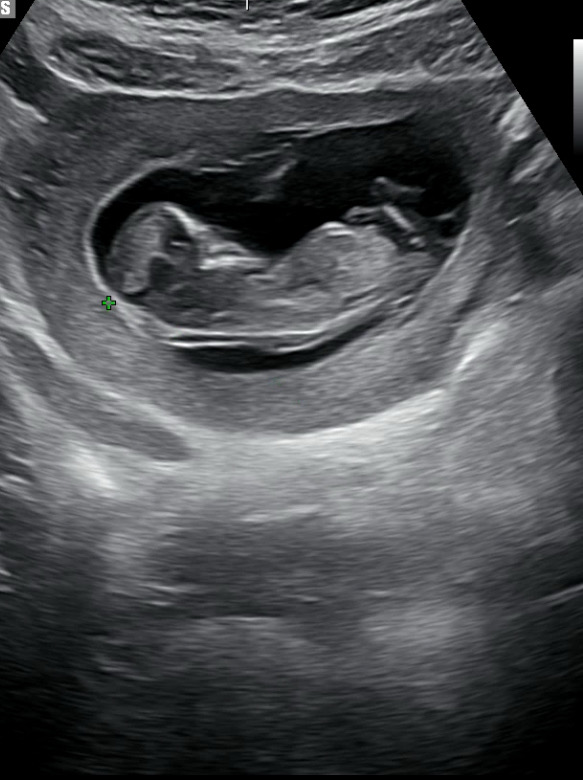

각도법 부탁드립니다!

12주 1일이에용! 아직 이르긴 한거같은데 궁금해서요ㅎㅎ

아들같아요!